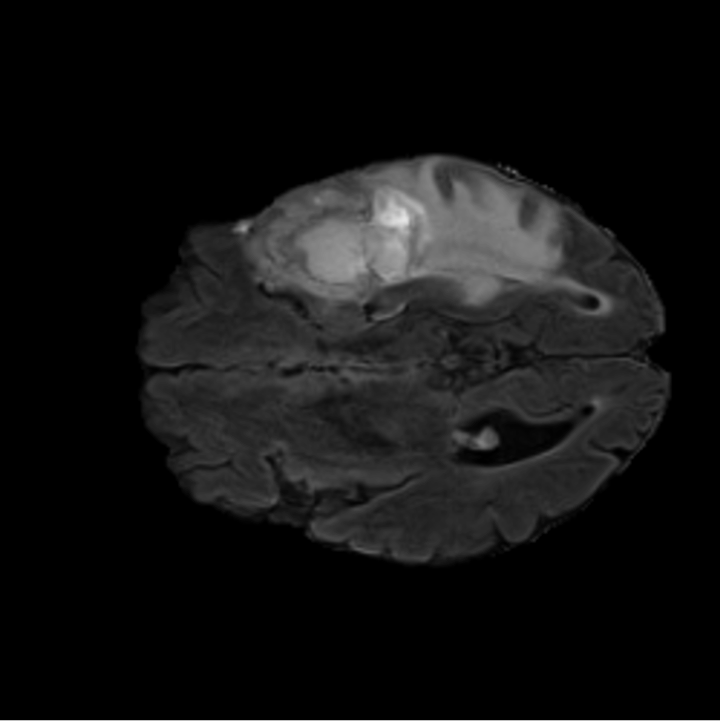

To see when and how X-Diffusion fails, we conducted an experiment on healthy brains (no tumour) using IXI dataset, by running an X-diffusion trained on BRATS brain tumor dataset. Our X-Diffusion achieved a PSNR of 35.86 dB on the IXI dataset despite being trained on the BRATS dataset. We then ran the tumour segmenter on the set of 582 healthy scans and corresponding generated MRIs. The segmenter predicted tumours in 9.9% of the real healthy brains and in 11.3% of the generated brain MRIs. Some of these tumor hallucination examples fron X-Diffusion generation are shown in Figure 10.

| Hallucination | Reference | Hallucination | Reference | Failure | Reference |